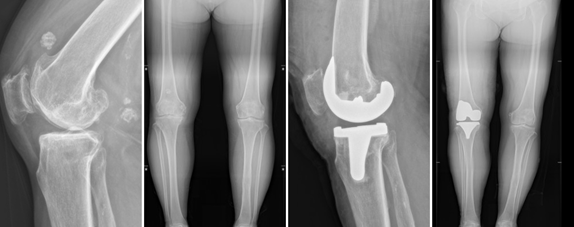

泸州71岁的陈奶奶,最近10年来一直饱受右膝关节疼痛的困扰,保守治疗效果不佳。

近日因疼痛显著加重、活动受限、影响睡眠来到西南医科大学附属中医医院骨伤科关节·足踝组就诊。医生诊断其为右膝重度骨性关节炎,需进行右侧人工全膝关节置换。

原来,国家人工关节集采政策于2022年4月20日起在四川正式落地执行,人工关节费用降价82%左右。以前人工关节费用接近4万元,陈奶奶因家里经济困难,一直没有做手术置换膝关节,而这次手术使用的人工关节才4000元不到。

4月21日,骨伤科关节·足踝组团队顺利为陈奶奶实施了右侧人工全膝关节置换手术。